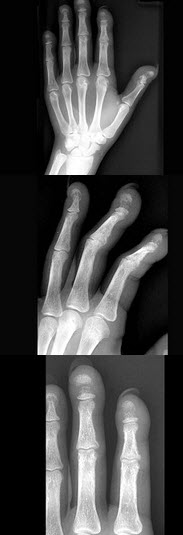

[单选题]女,41岁,慢性肾功能不全,结合图像,最可能的诊断是()A .白血病B .甲状旁腺功能亢进C .地中海贫血D .镰状细胞贫血E .骨关节结核

[单选题]女,41岁,慢性肾功能不全,结合图像,最可能的诊断是()A . 白血病B . 甲状旁腺功能亢进C . 地中海贫血D . 镰状细胞贫血E . 骨关节结核

[单选题]女,41岁,慢性肾功能衰竭,请结合图像,选出最可能的诊断()A .白血病B .甲状旁腺功能亢进C .地中海贫血D .镰状细胞贫血E .骨关节结核